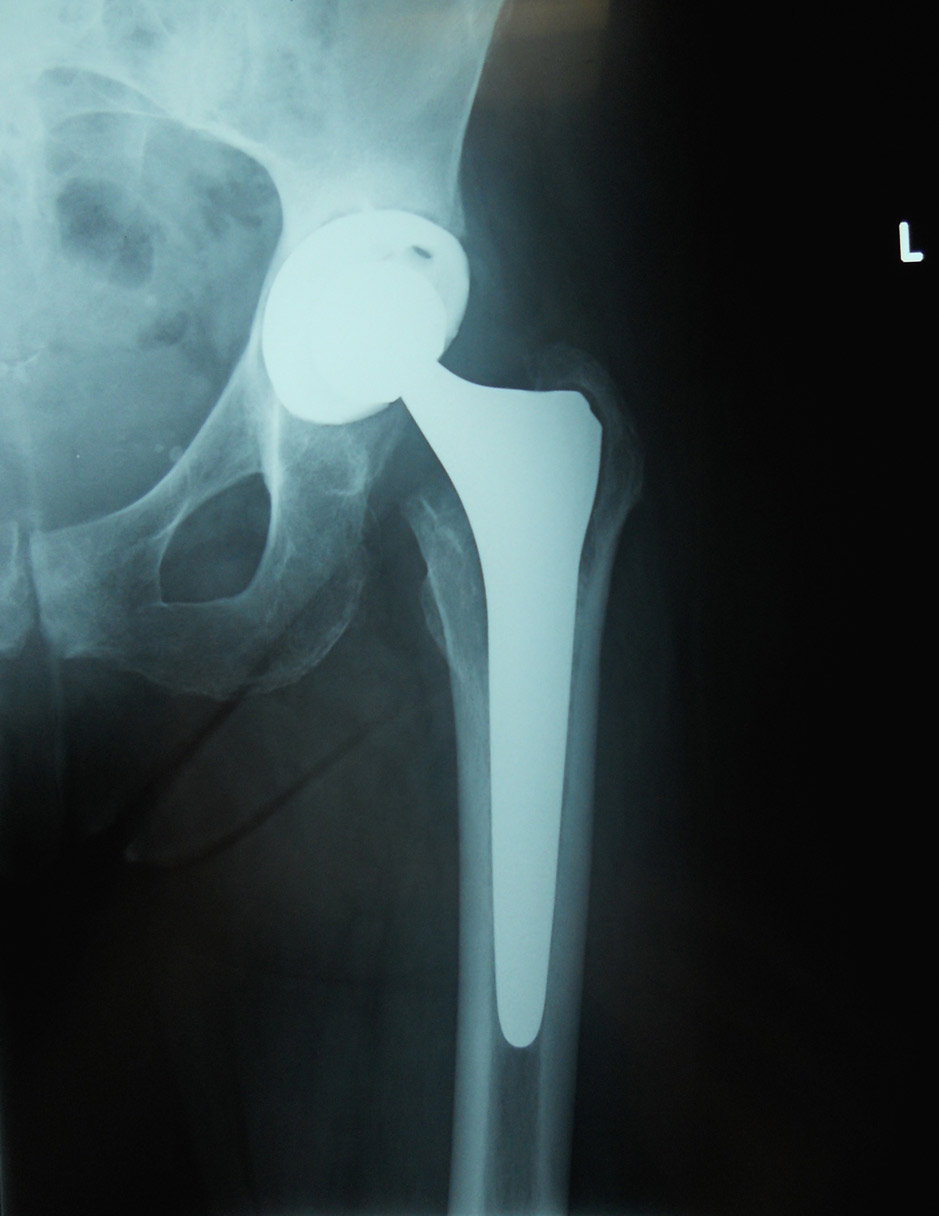

Fig. 2 Completa mobilizzazione con rotazione in senso antiorario e migrazione verso l’alto del cotile (frecce) con ampia usura dell’osso del bacino

Fig. 3 Risultato a 2 anni dell’intervento utilizzando un nuovo cotile con agganci sulla parte di bacino sana. Riempimento del grave difetto osseo del bacino con osso di banca (frecce)